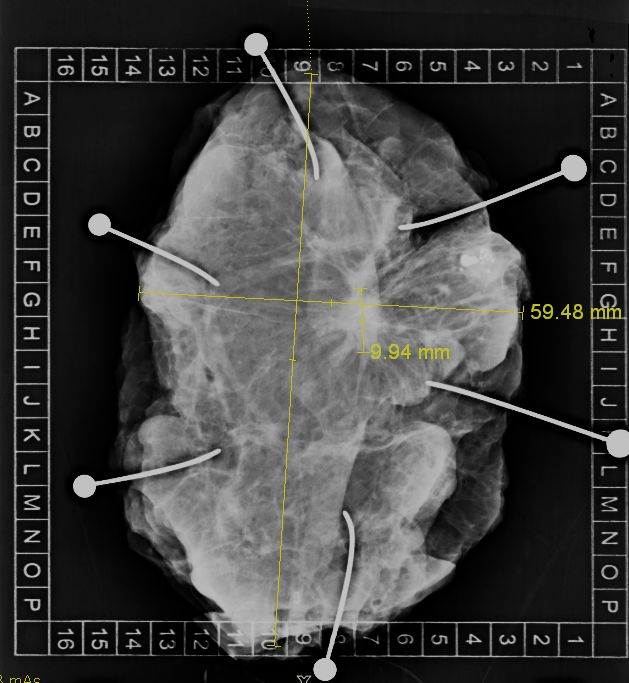

| allgemeines | Die Präparateradiographie soll sicherstellen, dass der Befund vollständig entfernt wurde. | ||

| Präparateradiographie |  Spezielle Aufnahmesysteme erlauben die exakte

geometrische Zuordnung der Schnittränder.![]()  | ||